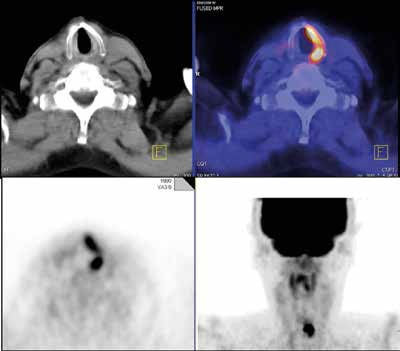

There are several sites of normal physiologic uptake of FDG -- most intense in the cerebral cortex and less intense in the myocardium, liver, kidneys, and bone marrow. The uptake can be highly variable in the lymphatic tissue, salivary glands, thymus, muscles, ovary, testes, activated brown fat, and the gastrointestinal tract. One of the most important challenges is to correctly differentiate physiological uptake from these normal variants, and this differentiation can prove a great source of potential false-positive interpretation.

In addition to normal variants, other challenges stem from FDG not being a tumor-specific substance; increased FDG uptake may be seen in a variety of other benign conditions such as inflammation, treatment-related effects such as thymic hyperplasia after chemotherapy, sarcoid-like reaction after immunotherapy, and inflammatory response after radiotherapy. Benign tumors such as thyroid/colorectal adenoma also can lead to false-positive interpretation. Conversely, false-negative interpretations are possible in cases of low tracer uptake or high neighborhood activity, Pfannenberg continued.

"To avoid misinterpretation, FDG uptake should always be precisely correlated with the high-resolution contrast-enhanced CT, and all available clinical and other imaging data should be taken into account," she noted.